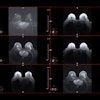

MR images are examples of T2-weighted, fluid-attenuated inversion-recovery (FLAIR), and precontrast T1-weighted images input into the deep-learning model. Postcontrast T1-weighted images (T1post) demonstrate areas of true-positive (white arrow) and false-negative (black arrow) enhancement. FN = false-negative classification of enhancement, FP = false-positive classification of enhancement, TP = true-positive classification of enhancement. Images courtesy of Radiology.Their deep-learning approach achieved a sensitivity of 78% (± 4%) and specificity of 73% (± 2.7) averaged across the five test sets for predicting contrast enhancement in each MRI slice. In addition, sensitivity was 72% (± 9%) and specificity was 70% (± 6%) in determining the presence of any enhancing lesions in an MS patient.